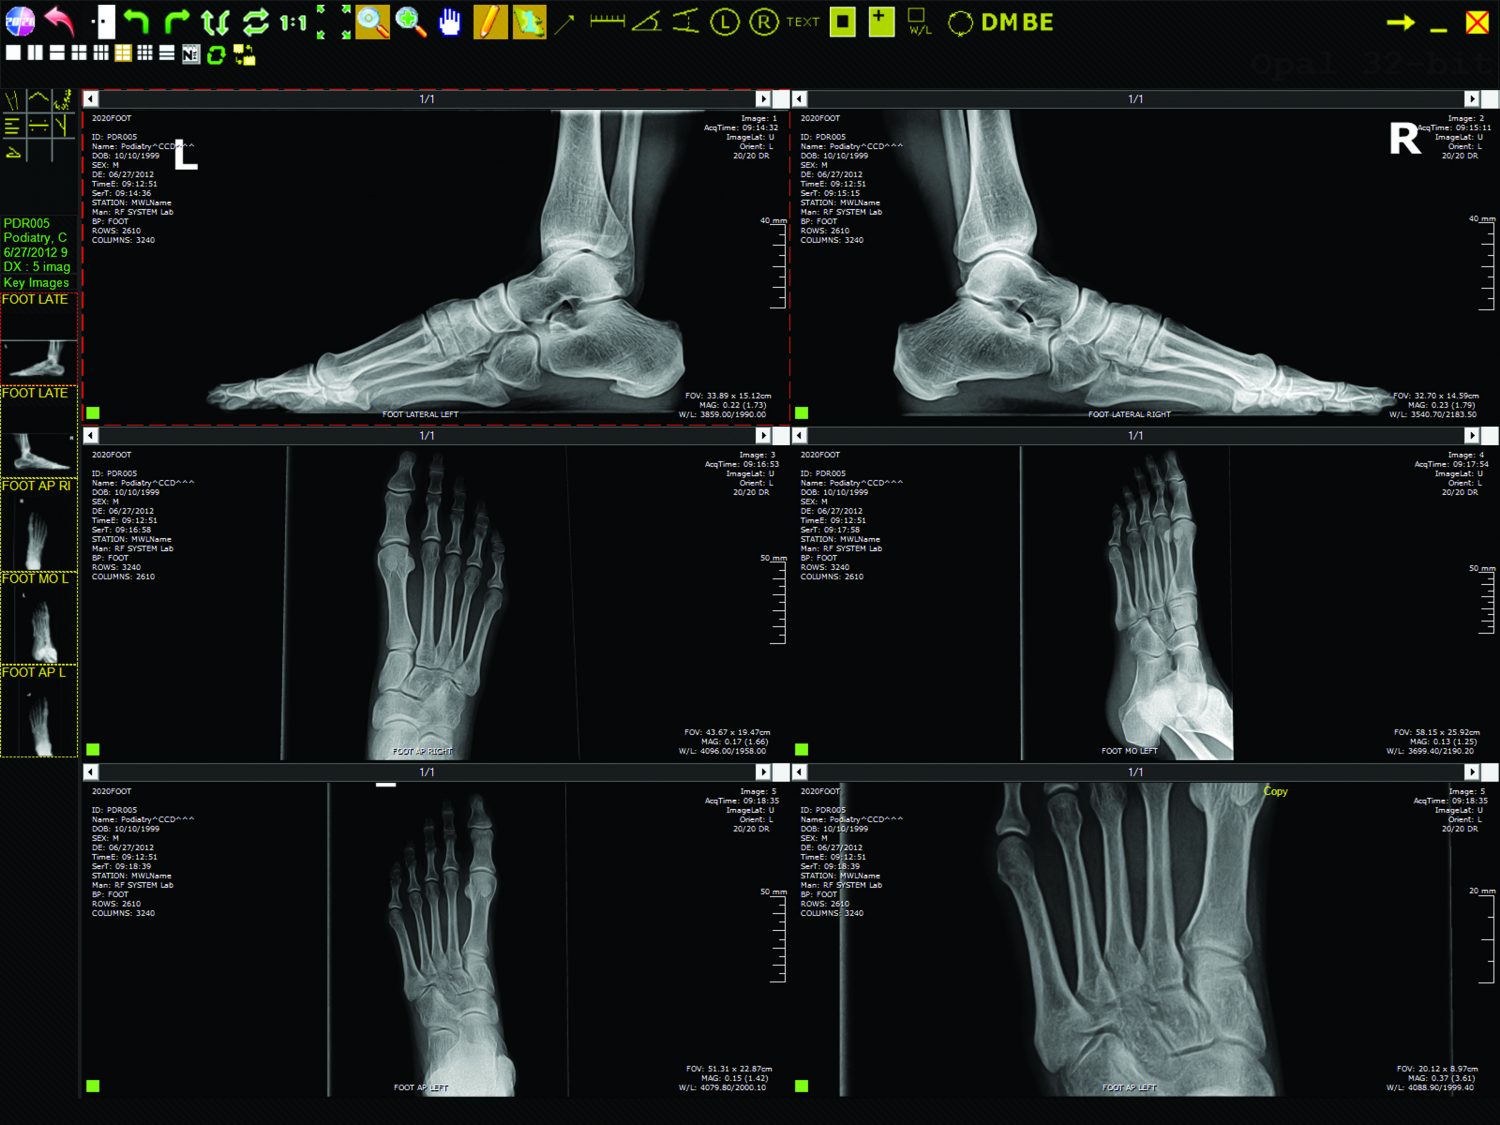

Le logiciel d'acquisition podiatrique Opal-RAD de 20/20 Imaging et le logiciel Mini-PACS sont préinstallés sur un ordinateur serveur Dell Business-Class avec un Poste de travail informatique mural conçu pour maximiser le flux de travail et économiser de l'espace au sol. L'écran de la visionneuse d'images de diagnostic offre une multitude d'outils et d'options pour aider à lire et à manipuler des images médicales à haute résolution. En plus de l'ensemble standard d'outils PACS, tels que le niveau de la fenêtre, le zoom, l'agrandissement, la rotation, le panoramique, l'inversion du contraste, le recadrage et l'outil d'amélioration des os, Opal-RAD propose un ensemble d'outils de podologie complet, calibré avec précision. La visionneuse d'images diagnostiques complète d'Opal-Rads permet aux utilisateurs de comparer rapidement et facilement des études antérieures (post / pré-op), dans une vue multiple côte à côte entièrement personnalisable avec des dispositions d'écran permettant jusqu'à 9 images par moniteur! La liste d'étude des patients, la recherche / requête, la barre d'outils, les privilèges utilisateur et l'affichage multiple côte à côte sont tous entièrement personnalisables. En plus de graver ou d'importer des études de patients sur disque, Opal-Pod vous permettra également d'importer plusieurs modalités d'archivage et de visualisation (Modality Work List). Opal-RAD fournit une mise à jour en direct sur tous les postes de travail, y compris l'invite de mise à jour du visualiseur, ce qui permet d'accéder rapidement et facilement aux études sur les patients sur plusieurs appareils compatibles Web. Opal-RAD est entièrement compatible DICOM, offrant des fonctionnalités d'envoi / réception DICOM et d'impression DICOM, en plus de la prise en charge de la liste de travail de modalité, permettant à ce système PACS complet d'être intégré à tout logiciel compatible DICOM.